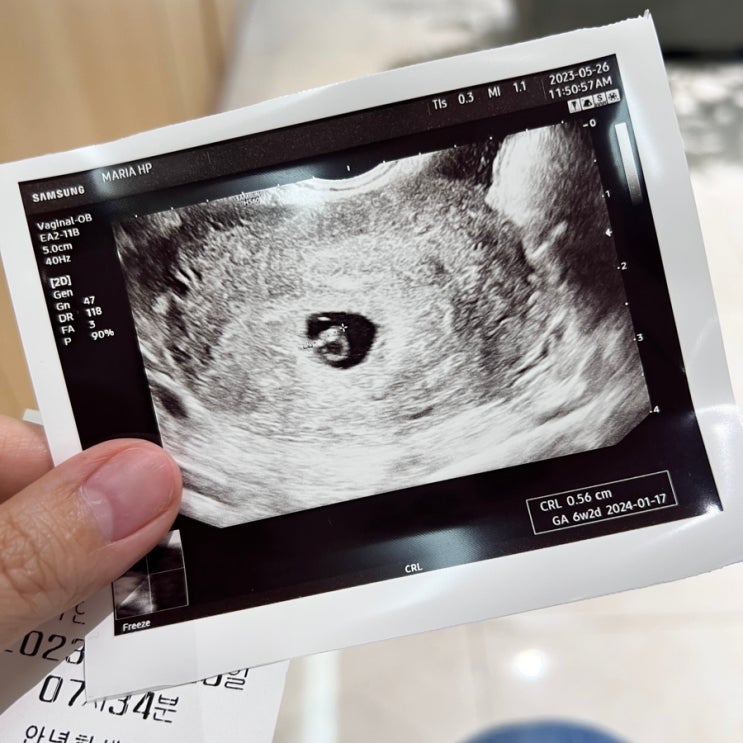

[임신일기/쑥쑥이 성장기록] 6주2일차, 심장이 콩닥콩닥 뛰는 걸 보고 왔다!

2023. 05. 26 (금) 포스팅 첫 사진은 물 마시기 인증사진 ✌? 지난 진료 때 아기집이 너무 작고 그게 양...